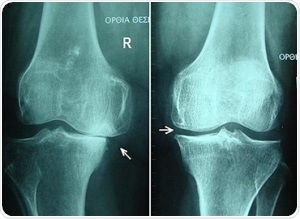

Knee osteoarthritis stages II and III by Harrygouvas at Greek Wikipedia. [CC BY-SA 3.0 or GFDL 1.3], from Wikimedia Commons